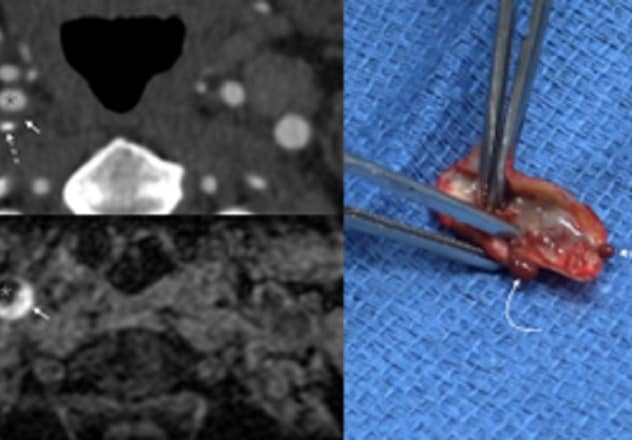

颈动脉粥样硬化性病变伴斑块内出血

颈动脉粥样硬化性病变伴斑块内出血

在左上角,初步的 CT 血管造影显示患者右颈动脉中有一个非狭窄斑块,其中有软质成分(短箭头所指),也有钙化成分(长虚线箭头所指)。星号所示为血管腔。左下角的随访 MRI 影像显示斑块内出血(如箭头所示)。星号所示为血管腔。右侧照片显示动脉粥样硬化性病变伴斑块内出血(如箭头所示),行颈动脉内膜切除术期间从患者身上切除病变。被切除的病变部分可以挤出血。